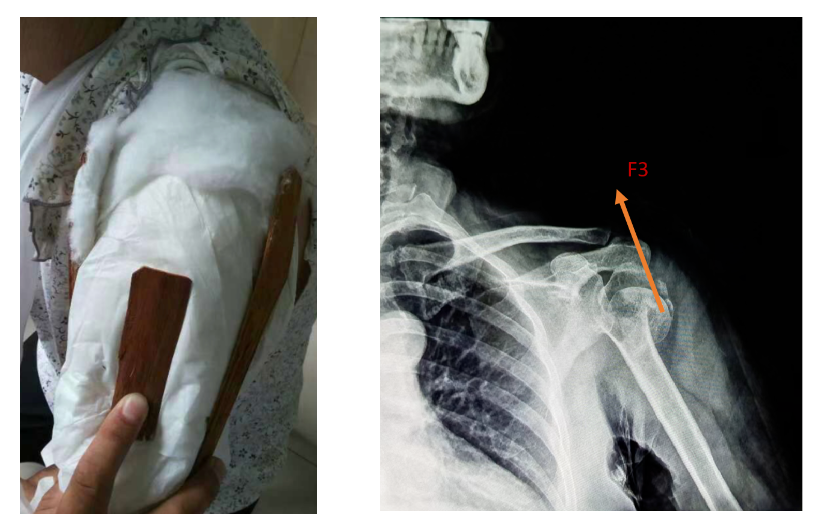

女,64岁,患肱骨近端粉碎性骨折10余天。骨折粉碎程度高,在躯干与肢干交界处的肱骨近端四部分骨折,成角角度约90度。

此时手法整复意义不大,又因家境困难,且患者本人惧怕手术,于是我们开启了医患焦虑的慢慢保守治疗之路,在“错位骨折如何得到最大化纠正”的力学固定上动足了脑筋。

第一部分的力由腋下处的夹板(笔者特别制作)提供的一个向上的力(F1),另一个则是支撑远端骨折的垂直肱骨干向上的力(F2)。

第二部分的力在断端下缘处额外增加一个小树皮,使之有一个向上的托举力(F3)。

第三部分的力通过“胶布墙”制造的牵拉力nF4,力的方向指向颈肩部方向。这个力至关重要,假如一条胶布的牵拉力是100克,那么20条胶布组成的“胶布墙”就有2000g了。

第四部分的力F5。肘与前臂夹角110°左右悬挂,使得肱骨干重力在肱骨干上的分力(mg余弦∠身体与上臂之夹角)较大,同时使在断端嵌插处得到牵拉修复的空隙。

诸力使得近断端沿肱骨干向上,远断端沿着肱骨干向下,骨折修复因子在这样的力学系中进行着正相“光合作用”——即成骨细胞、破骨细胞沿力学方向进行最大化的修复与重建。

采用此方法固定两月半,再拆除夹板外固定一个月后,在这四部分力的作用下,患者肱骨近端四部分骨折基本愈合,骨折成角90度在沿着其力的方向上得到最大纠正,患者已可以在家里骑三轮车干活。本次治疗共计花费约数千元。